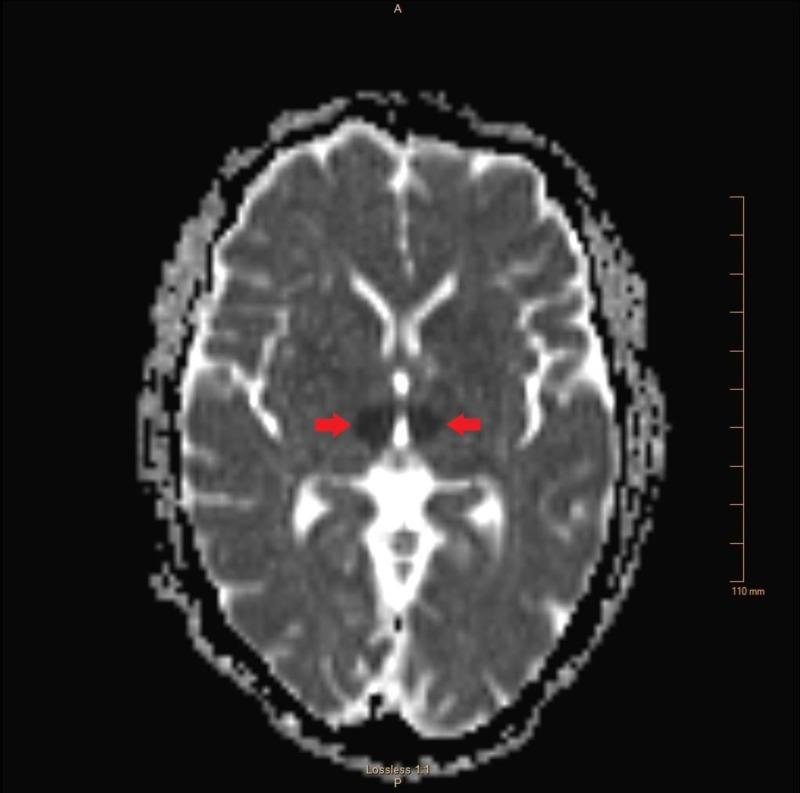

The artery of Percheron (AOP) is a variant of the paramedian thalamic vasculature that supplies blood to the medial aspect of the thalamus and the rostral midbrain. The presentation of an infarct in this territory varies widely and is often characterized by nonspecific neurological deficits, with altered mental status, decreased level of consciousness, and memory impairment being among the most common. AOP infarcts are often missed on initial computed tomography (CT) scan, and additional imaging is usually not done due to low suspicion for stroke in most cases. There have been an increasing number of reports of AOP infarction, illustrating the diversity of clinical presentations and the challenge this presents to clinicians in the acute setting. Lacking the classic signs of stroke, many of these patients experience a delay in recognition and treatment, with the majority of diagnoses occurring outside the tissue plasminogen activator (tPA) window. This case highlights the unusual presentation and diagnostic difficulty of a patient with an AOP infarct, and serves as a reminder to include thalamic pathology in patients presenting with vague neurological symptoms and no obvious signs of stroke.

佩谢隆动脉(AOP)是丘脑旁正中脉管系统的一种变异,为丘脑内侧和中脑前部供血。该区域梗死的表现差异很大,通常以非特异性神经功能缺损为特征,其中意识状态改变、意识水平下降和记忆障碍最为常见。AOP梗死在初次计算机断层扫描(CT)时常常漏诊,而且在大多数情况下,由于对中风的怀疑度低,通常不会进行进一步的影像学检查。关于AOP梗死的报道越来越多,这说明了临床表现的多样性以及在急性情况下给临床医生带来的挑战。由于缺乏中风的典型体征,许多此类患者在识别和治疗上出现延迟,大多数诊断发生在组织纤溶酶原激活剂(tPA)治疗窗之外。本病例突出了一名AOP梗死患者的不寻常表现和诊断困难,并提醒在出现模糊神经症状且无明显中风体征的患者中要考虑丘脑病变。